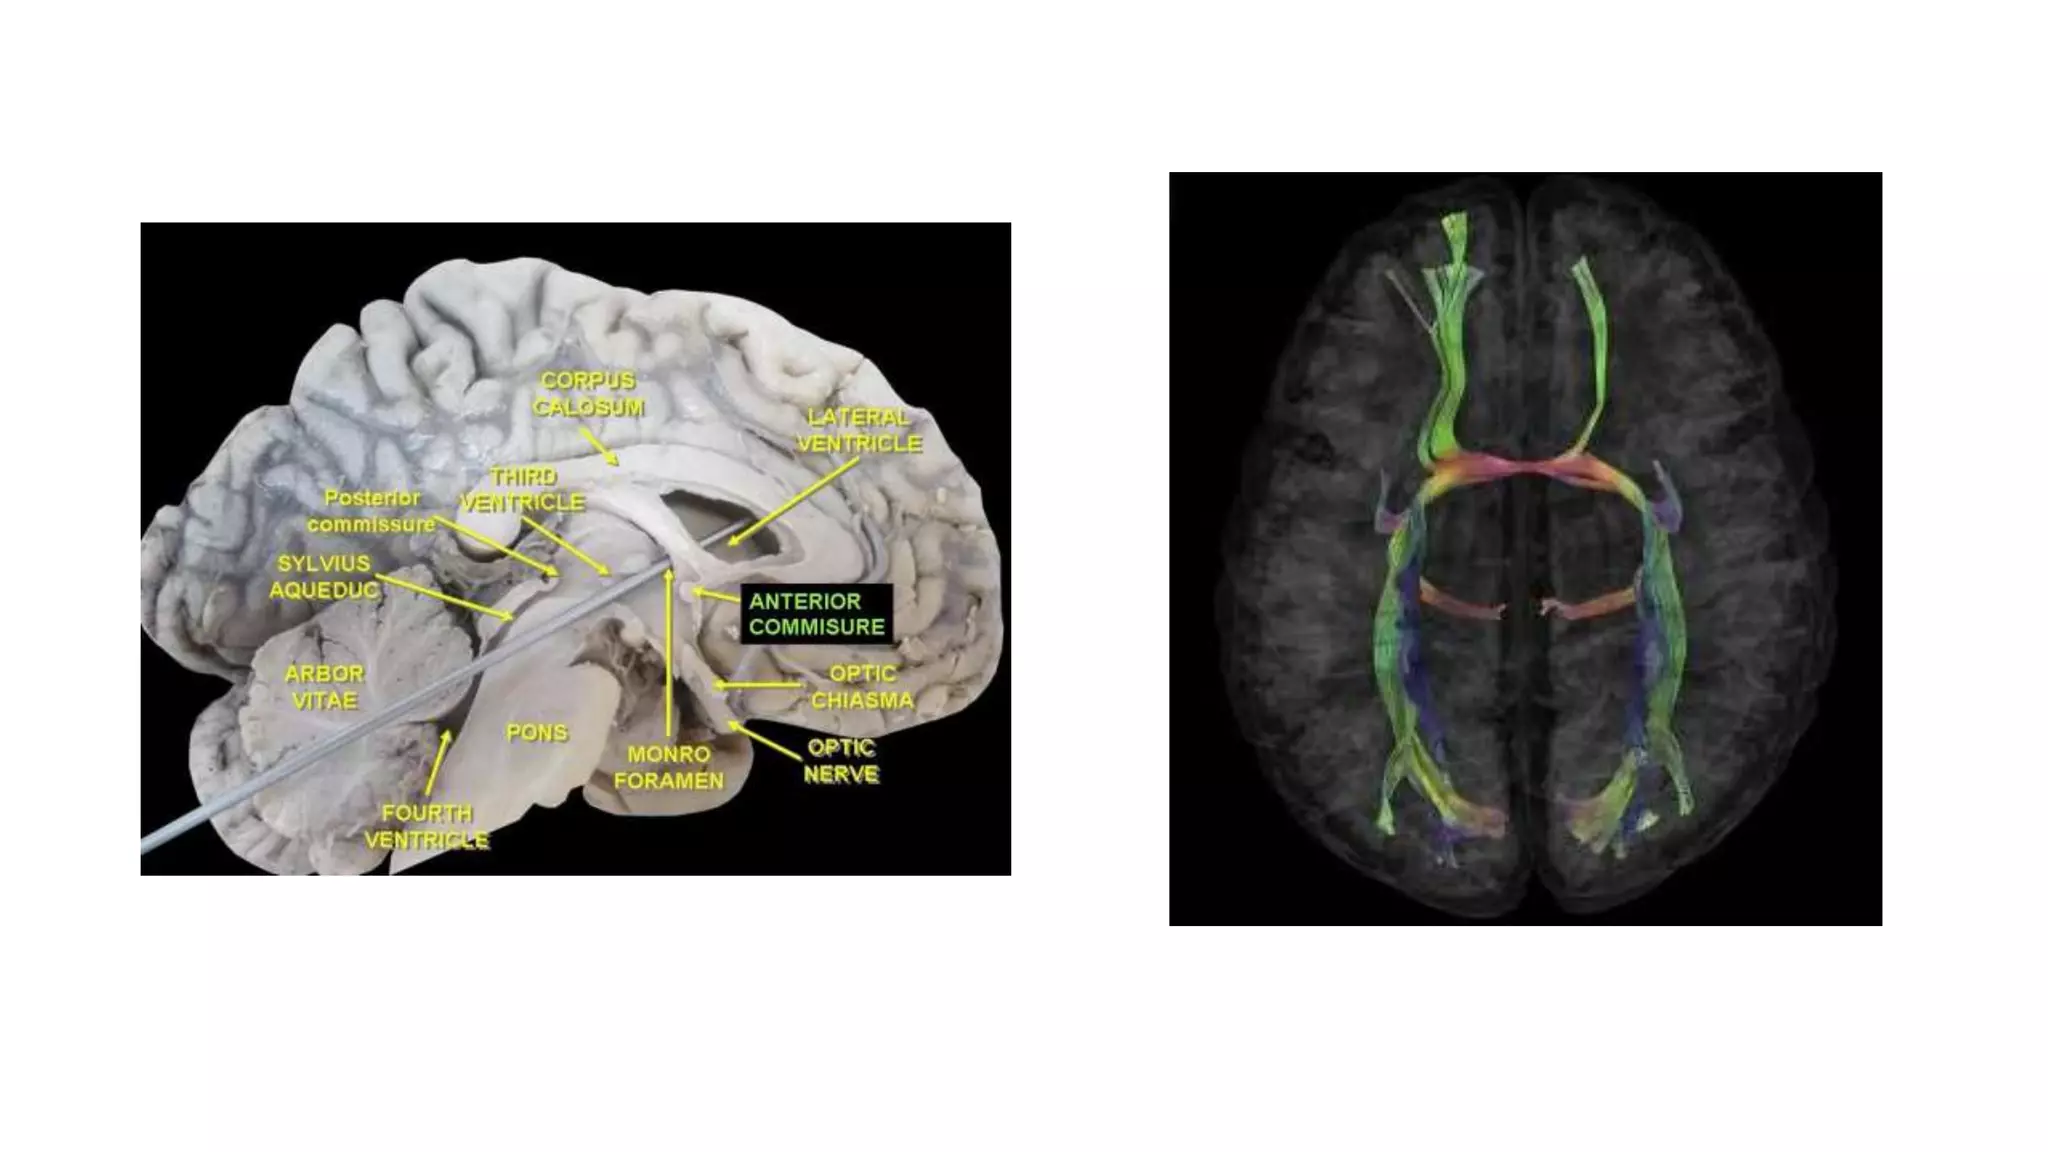

Commissural fiber: Anterior commissure

 This tract connects two temporal

lobes of both hemispheres & placed in

front of the columns of the fornix

 It crosses through the lamina

terminalis

 Its anterior fibers connect the

olfactory bulb and nuclei, its posterior

fibers connect middle and inferior

temporal gyri

Commissural fiber : corpus callosum

The corpus callosum is the largest commissure of the

brain connecting the cerebral cortex of the two cerebral

hemispheres

Concave inferior aspect of corpus callosum is attached with

the convex superior aspect of the fornix by the septum

pellucidum

Parts of the corpus callosum

• Rostrum, Genu, Trunk & Splenium

Commissural fiber: Anteriorcommissure  This tract connects two temporal lobes of both hemispheres & placed in front of the columns of the fornix  It crosses through the lamina terminalis  Its anterior fibers connect the olfactory bulb and nuclei, its posterior fibers connect middle and inferior temporal gyri

Commissural fiber :corpus callosum The corpus callosum is the largest commissure of the brain connecting the cerebral cortex of the two cerebral hemispheres Concave inferior aspect of corpus callosum is attached with the convex superior aspect of the fornix by the septum pellucidum Convex superior aspect is covered by a thin layer of grey matter, the indusium griseum, embedded in which are the fibre bundles of bilateral medial and lateral longitudinal striae. Superior aspect of corpus callosum is covered on each side by cingulate gyrus from which it is separated by a callosal sulcus.

Parts of thecorpus callosum • Rostrum, Genu, Trunk & Splenium The fibres connecting the occipital lobes sweep backwards on either side above the calcarine sulcus forming a large fork-like structure, the forceps major Splenium The trunk is the main (middle) part. Its fibres connect most of the frontal and anterior parts of the parietal lobes of the two cerebral hemispheres. Trunk The fibres of genu sweep (curve) forwards on either side into the anterior parts of the frontal lobes, forming a fork- like structure, the forceps minor. Genu Rostrum forms the floor of the anterior horn of lateral ventricle and its fibres extends inferiorly to connect the orbital surfaces of the two frontal lobes. Rostrum

• #40 llustration (A), gross dissection (B), directional map (C), and tractogram (D). The largest WM fiber bundle, the corpus callosum connects corresponding areas of cortex between the hemispheres. Close to the midline, its fibers are primarily left-right oriented, resulting in its red appearance on this DTI map. However, callosal fibers fan out more laterally and intermingle with projection and association tracts, resulting in more complex color patterns. Sagittal directional map of the corpus callosum (arrowheads) (A) and tractogram (B).